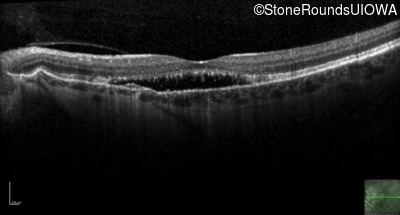

Age at visit: 58 years